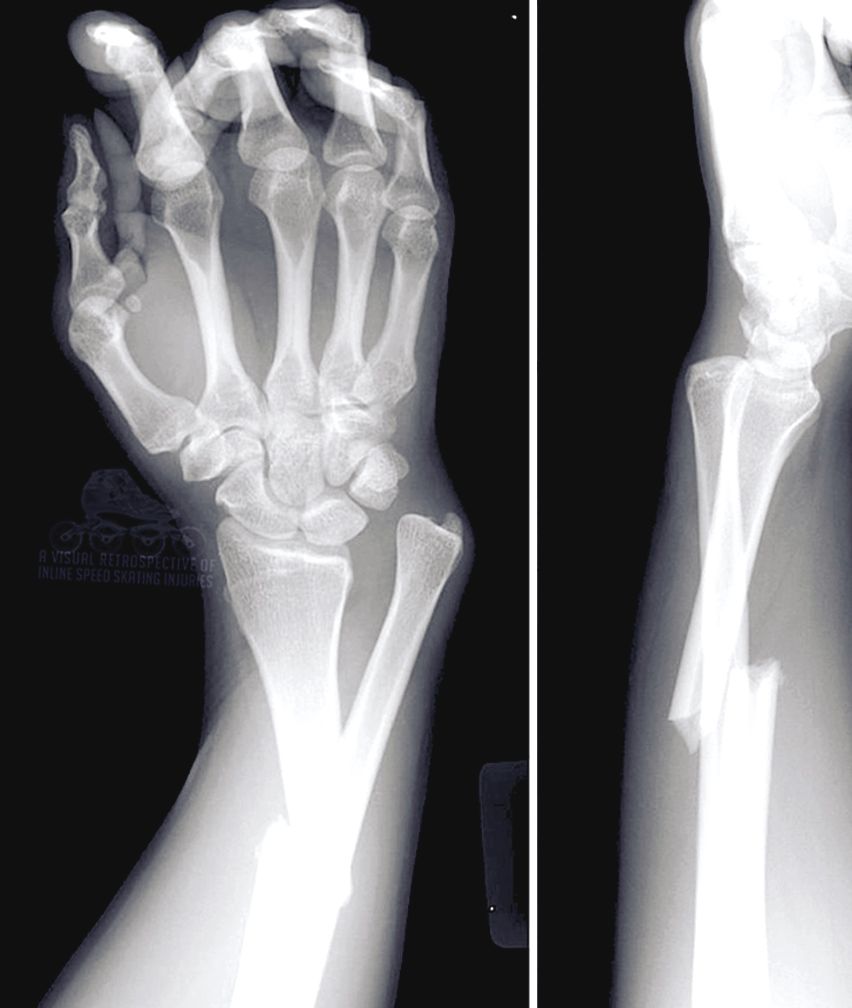

Чтобы быстрее сросся перелом руки

Чтобы быстрее сросся перелом руки 109 фото